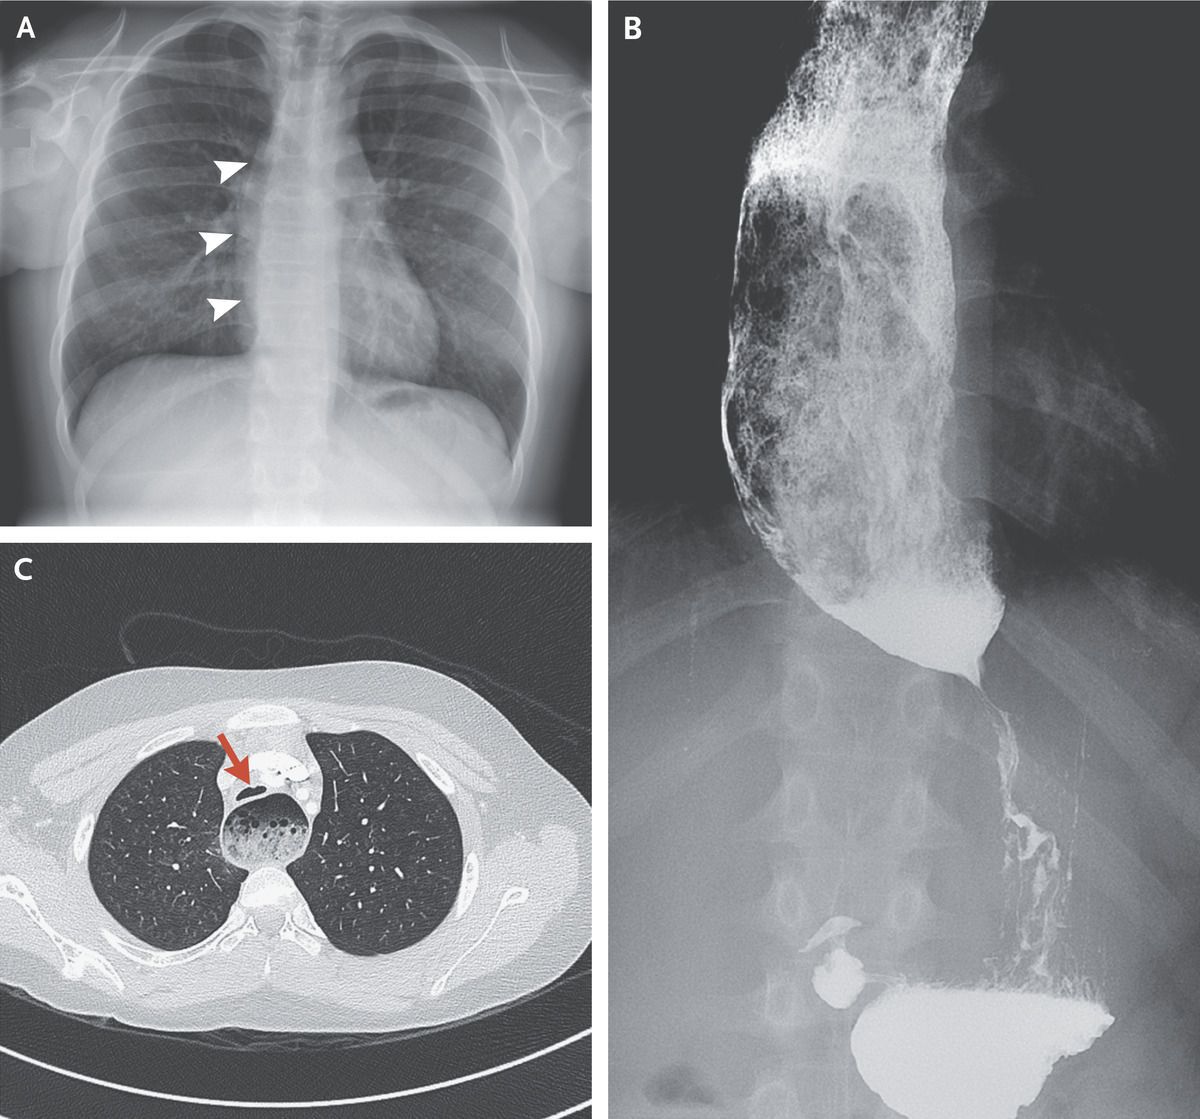

A 13-year-old boy with allergic rhinitis presented to his family physician with a 6-month history of nocturnal cough and nighttime awakenings. The cough had not abated with antibiotic therapy or with medications to treat asthma, gastroesophageal reflux, or postnasal drip. Over the preceding month, he had also begun to have posttussive regurgitation of partially digested food. The physical examination was normal. A radiograph of the chest showed a double contour at the right heart border and widening of the mediastinum, findings that suggested esophageal dilatation (Panel A, arrowheads). A timed esophogram with the use of barium confirmed a dilated esophagus with acute tapering at the gastroesophageal junction (Panel B). Computed tomography of the chest with the use of contrast material revealed a dilated esophagus with intraluminal food and compression and anterior displacement of the trachea (Panel C, arrow). Achalasia may manifest as a nocturnal cough owing to reflux of undigested food during recumbency and is an important consideration in patients whose condition does not improve with therapies for more common disorders. The patient was referred to the gastroenterology clinic and underwent a laparoscopic Heller myotomy with fundoplication. He had no postoperative complications, and his symptoms resolved.